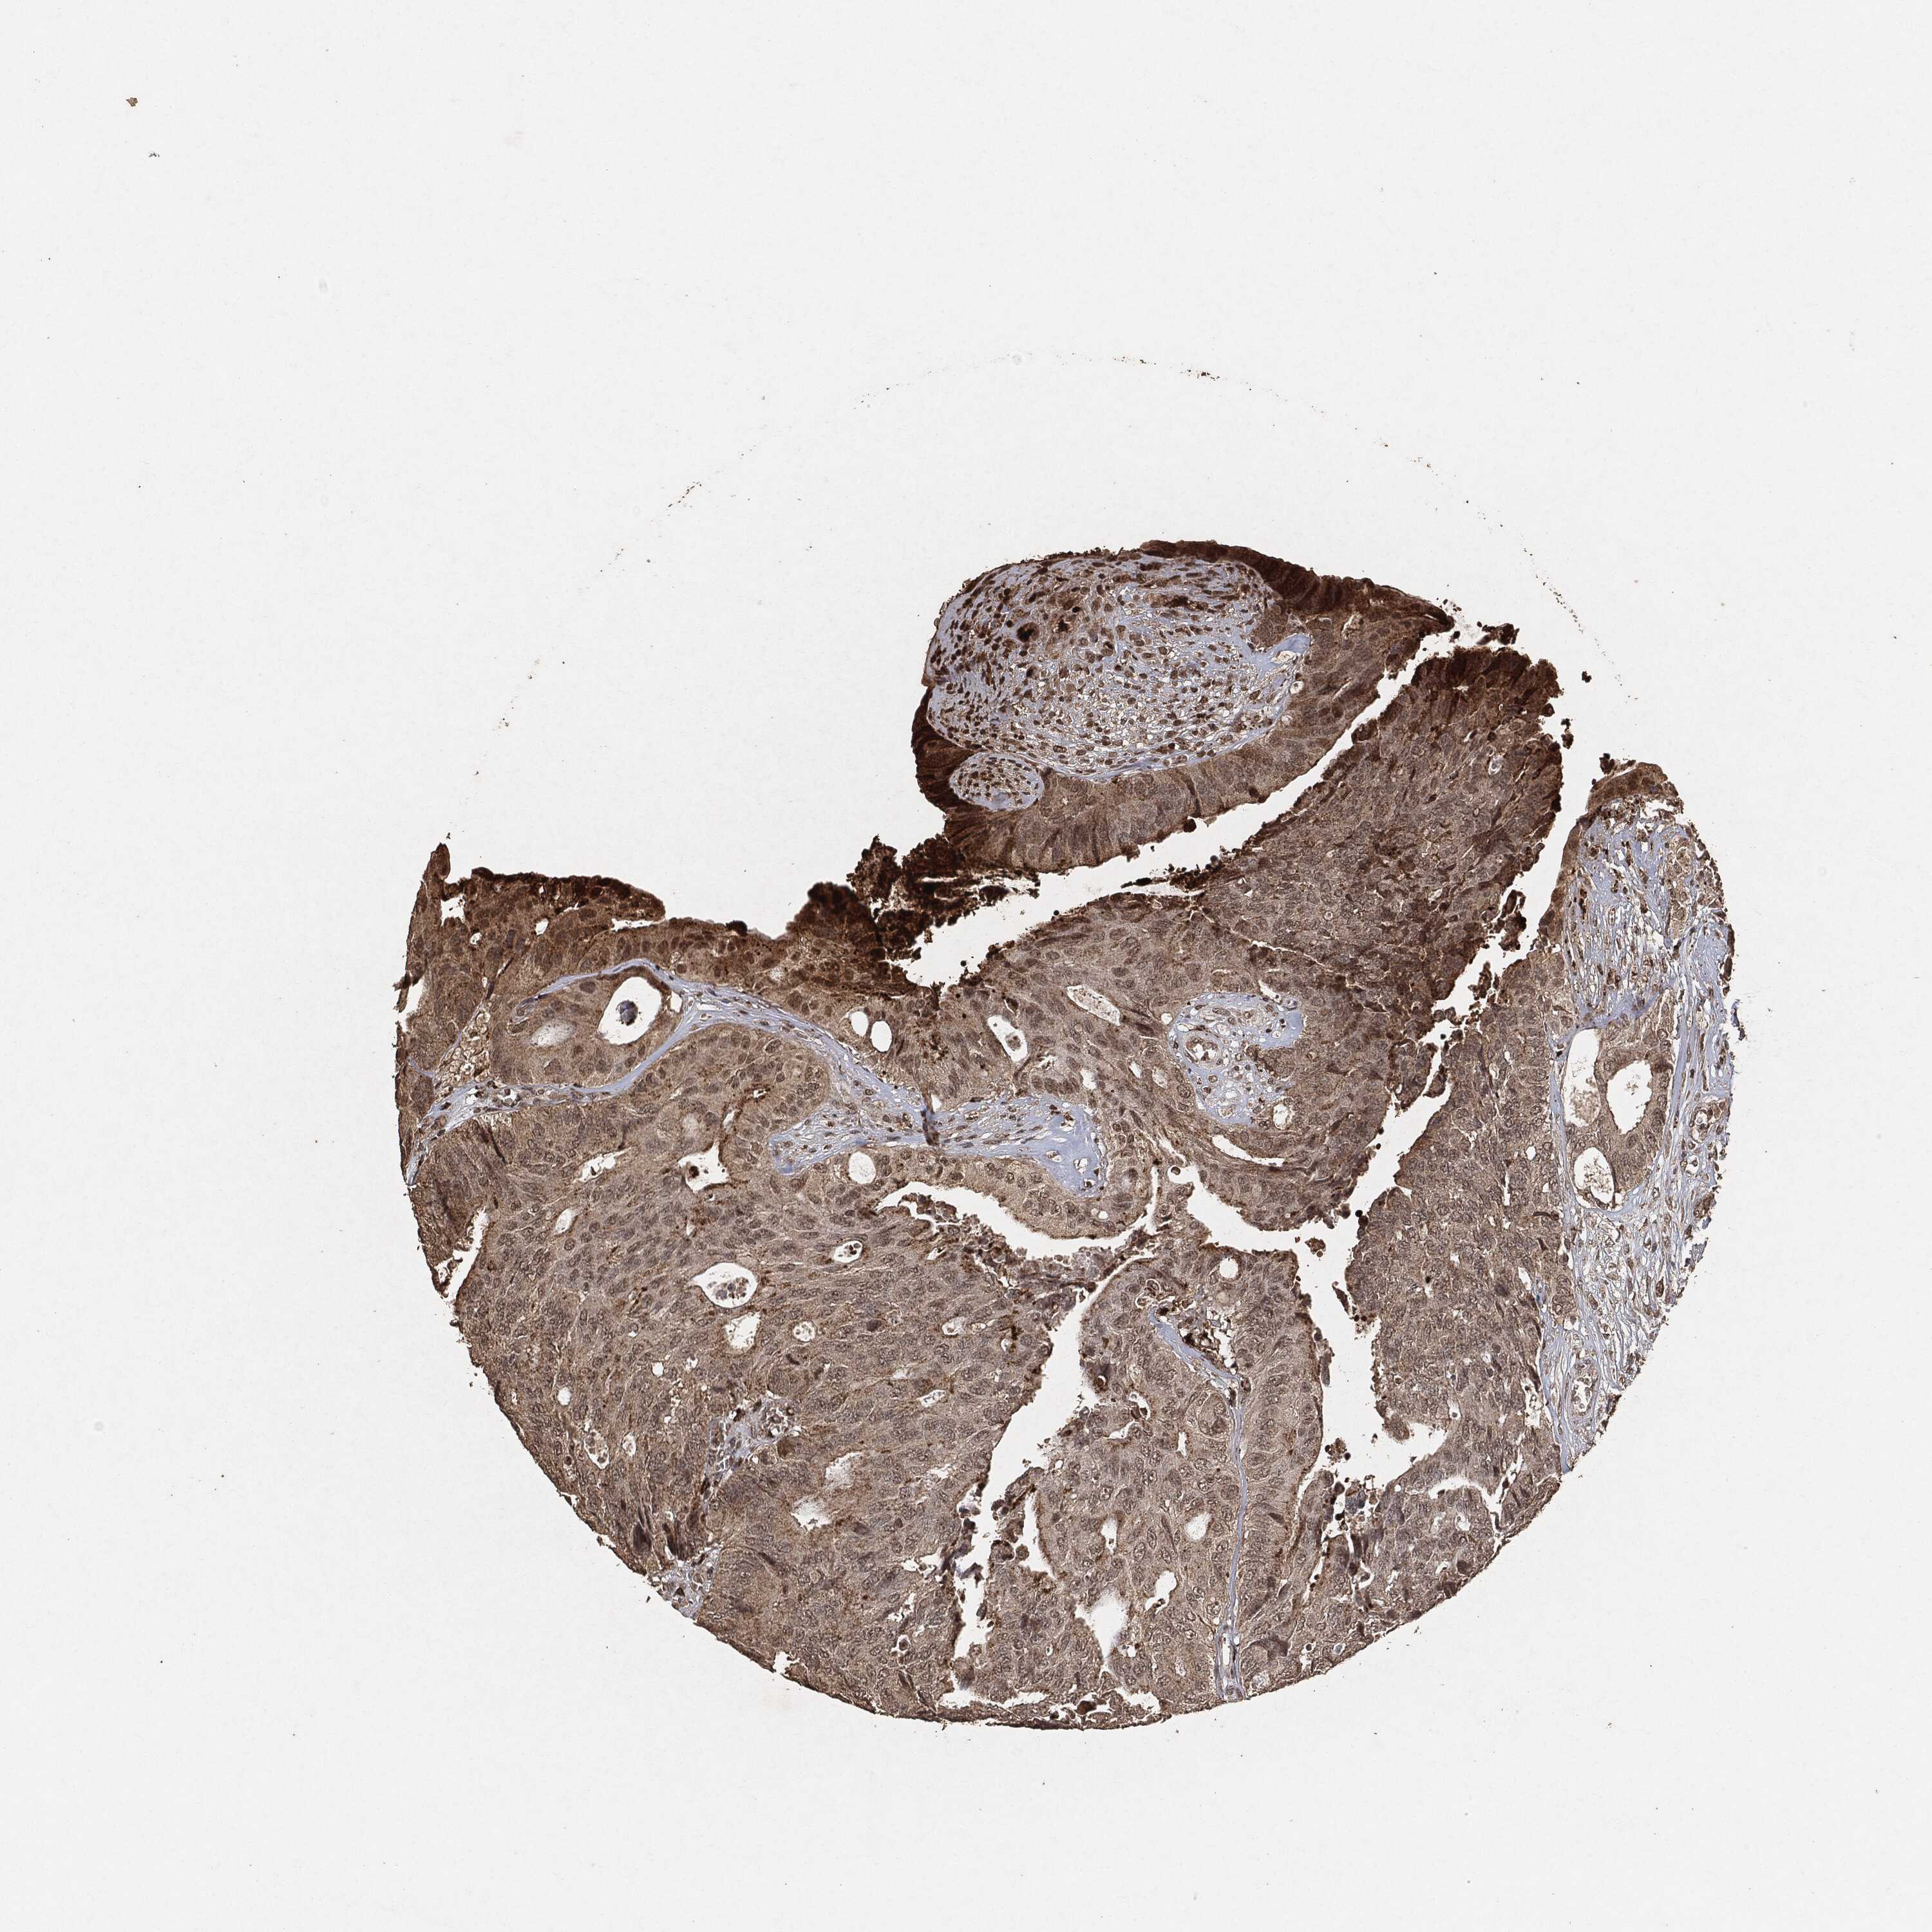

CANCER COLORECTAL CANCER Show tissue menu

Colorectal cancer

Human cancer

Colon adenocarcinoma